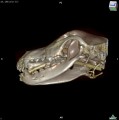

CT - angiografie (kočka)